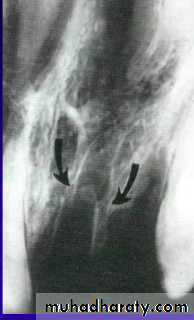

Replacement Resorption(Ankylosis)

Direct union of bone and root

Resorption of root

Replacement with bone

Direct result of loss of vital PDL

Inflammatory Resorption-Resorption of cementum and dentin

-Inflammatory reaction in the periodontal

ligament

Inflammatory resorption, replacement resorption ankylosis and tooth submergence are potential complications when avulsed tooth are replanted